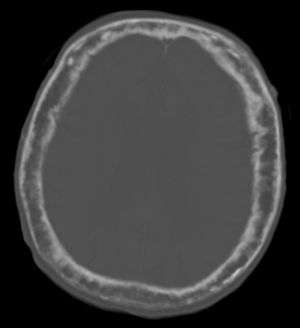

"This 92 year-old male patient presented for assessment of sudden inability to move half their body. An incidental finding was marked thickening of the calvarium. The diploic space is widened and there are ill-defined sclerotic and lucent areas throughout. The cortex is thickened and irregular. The findings probably correspond to the “cotton wool spots” seen on plain films in the later stages of Paget’s disease." | |